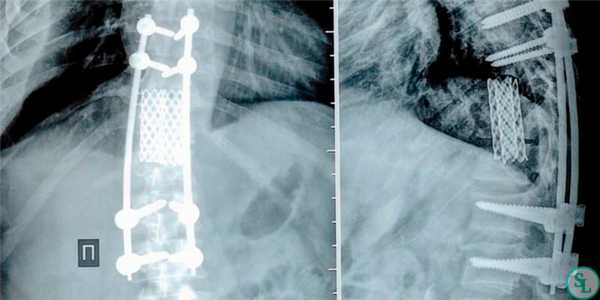

- Выбор межтелового опорного трансплантата. Ввиду значительной болезненности в зоне забора достаточно крупного по размерам костного аутотрансплантата (трикортикальный трансплантат из крыла подвздошной кости, малоберцовая кость или васкуляризированный фрагмент ребра) все большее распространение получают альтернативные методы реконструкции передней колонны позвоночного столба. Несмотря на возможные риски секвестрации и замедления процесса формирования костного блока хорошие результаты, согласно данных недавних исследований, получены при использовании с целью передней реконструкции после адекватного дебридмента активного очага инфекции аллокостных трансплантатов и титановых кейджей.

- Использование стабилизирующих конструкций в условиях инфекционного процесса. Опасения, связанные с использованием в условиях активного инфекционного процесса стабилизирующих конструкций, привели к тому, что наиболее распространенной и эффективной практикой на сегодняшний день является вентральная реконструкция позвоночника с использованием опорных костных трансплантатов и задняя его стабилизация из отдельного доступа. В недавних исследованиях, однако, показано, что вентральная стабилизация позвоночника при неспецифических и специфических инфекционных его поражениях также может быть эффективной.

Дискэктомия (удаление разрушенного диска) и корпэктомия (удаление фрагмента тела позвонка) позволяют полностью очистить пораженные ткани. Внедрение распорочных трансплантатов (вырезанных из костных структур, взятых в ребрах или гребне подвздошной кости) позволяет хрящевым тканям начать восстанавливаться, а фиксирующие позвоночный столб титановые конструкции временно снимут нагрузку на пострадавшие позвонки. Реабилитация занимает от 3 месяцев до полугода.